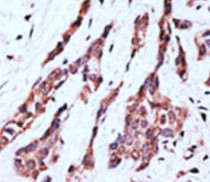

ARG54850 anti-LPAR2 / EDG4 antibody (N-term) IHC-P image

Immunohistochemistry: Formalin-fixed and paraffin-embedded Human breast cancer tissue stained with ARG54850 anti-LPAR2 / EDG4 antibody (N-term).